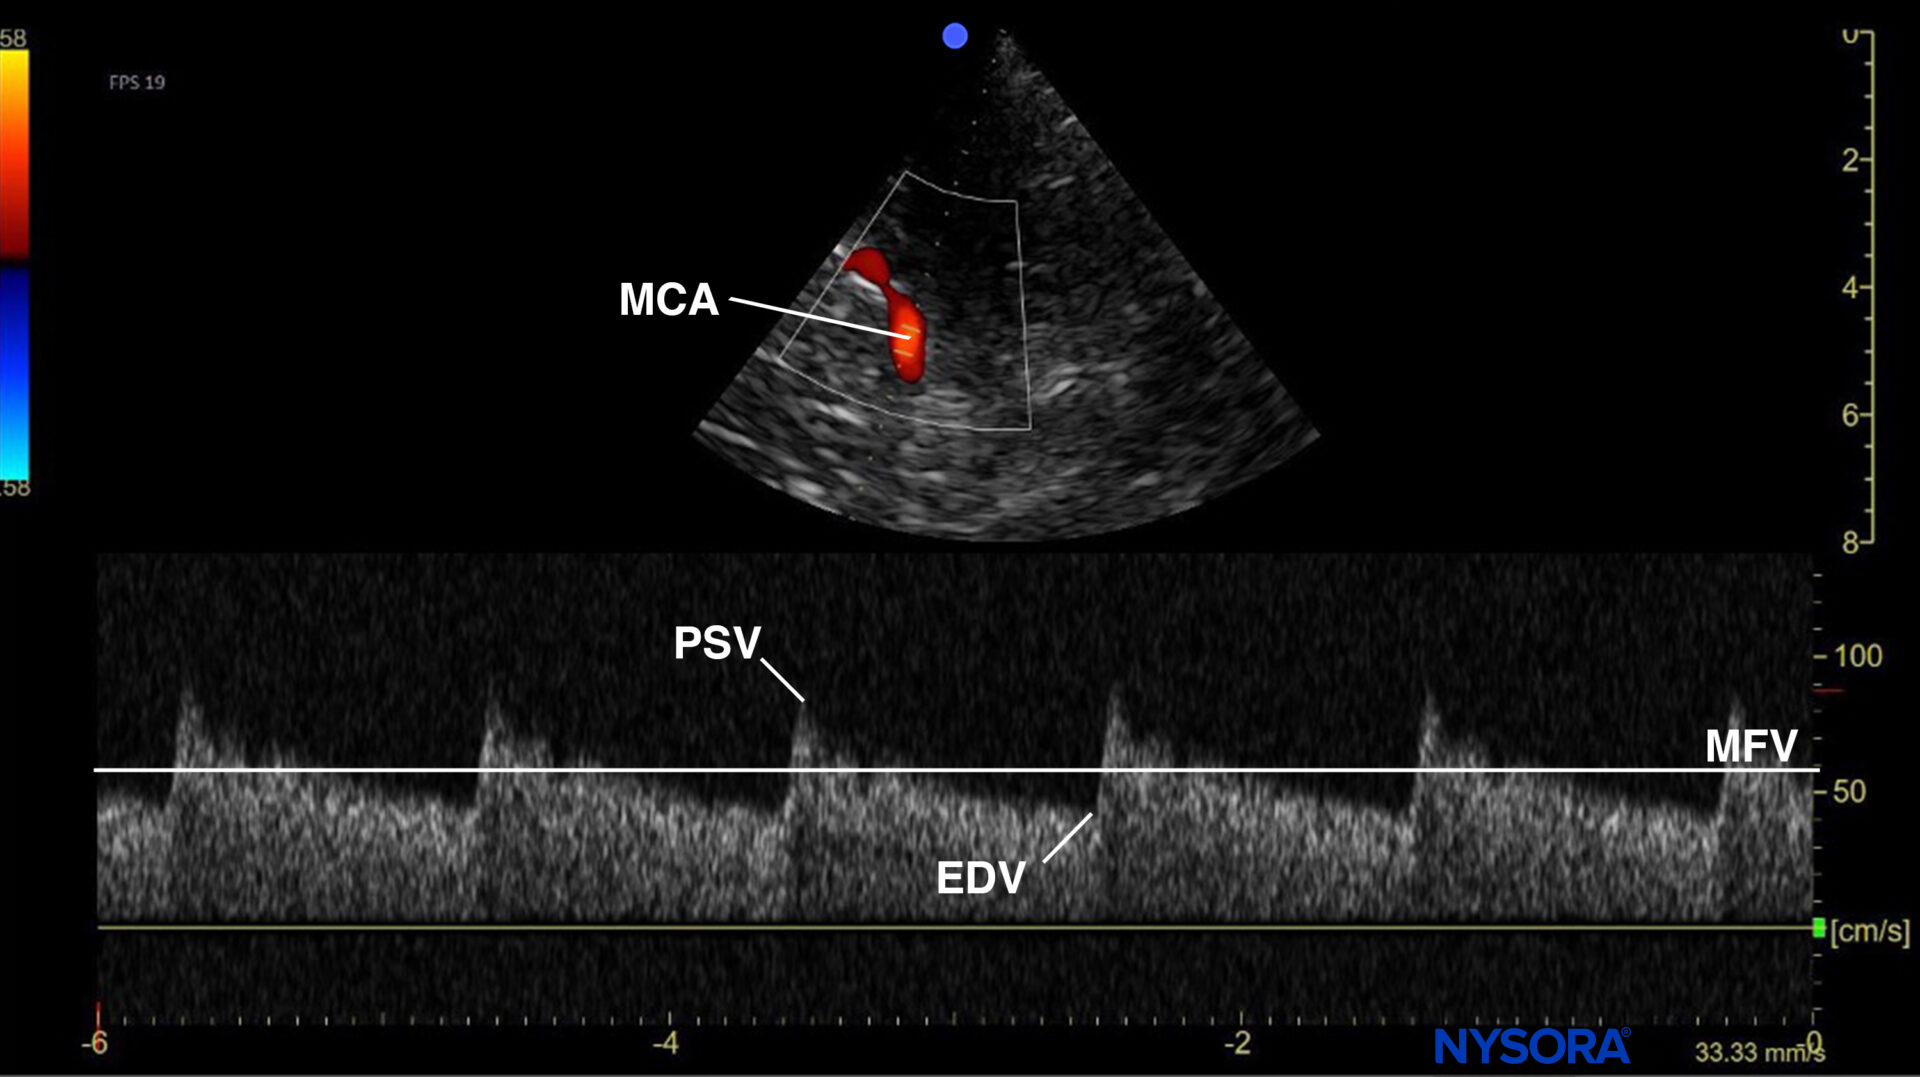

- Use the mesencephalic plane and activate pulsed wave Doppler. Position the Doppler gate on the middle cerebral artery (MCA) and trace the flow velocities.

Mesencephalic plane pulsed wave Doppler with the Doppler gate on the middle cerebral artery (MCA). Evaluation of flow velocities in the MCA. PSV, peak systolic velocity; EDV, end-diastolic velocity; MFV, mean flow velocity.